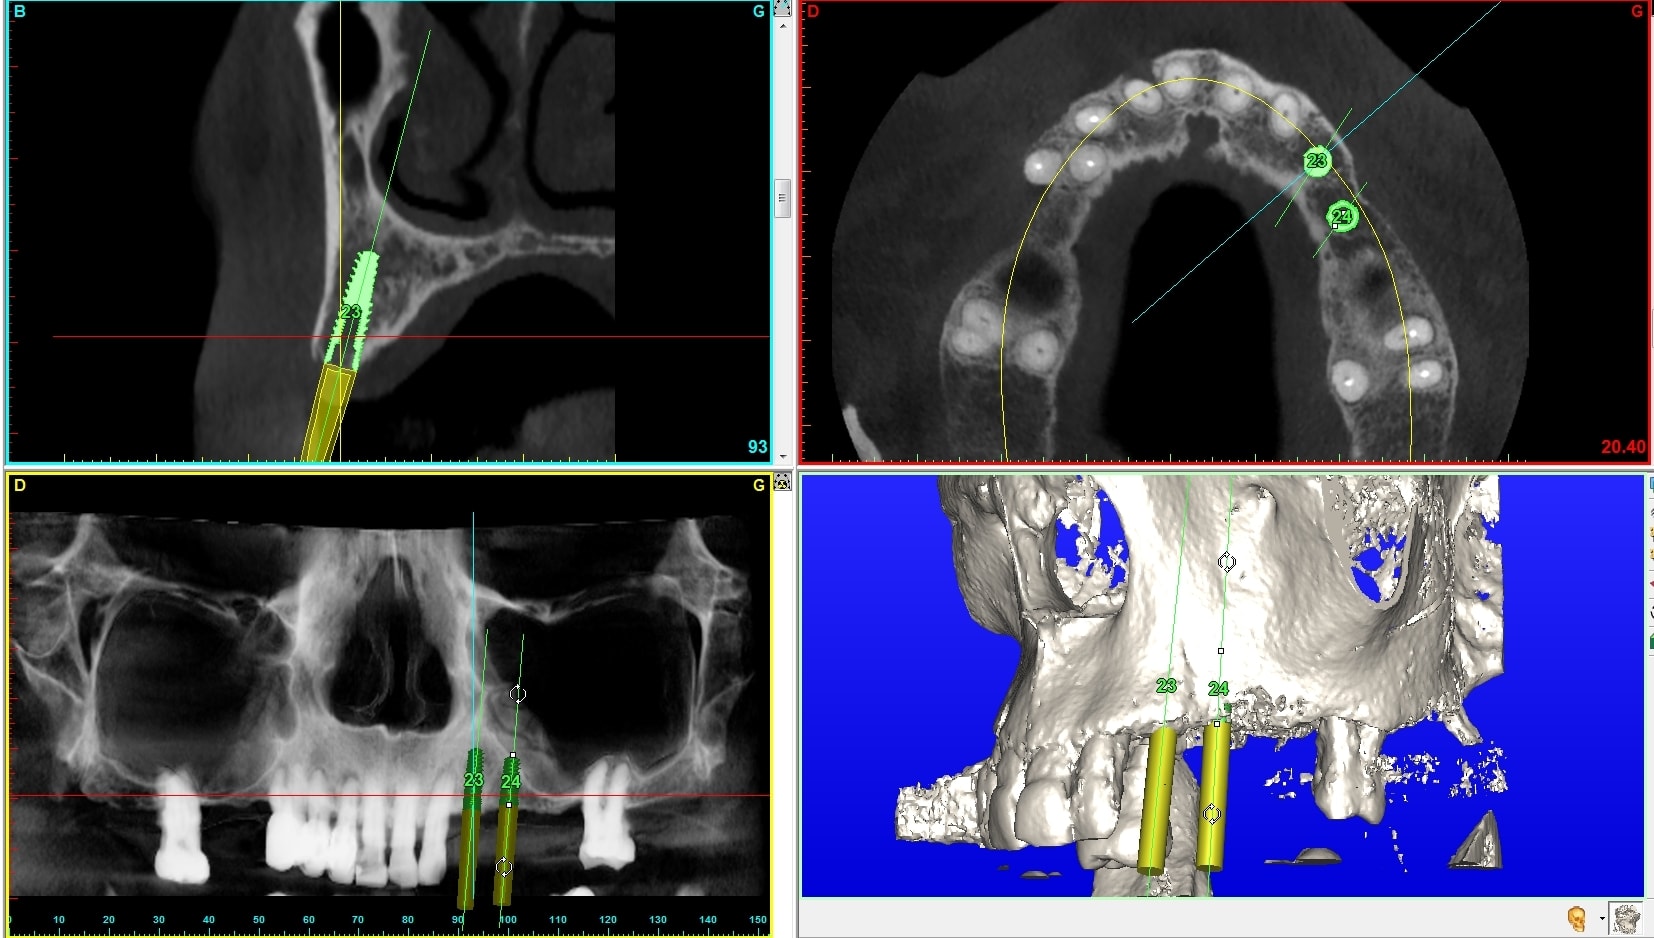

Je préfère te donner une réponse en images. Maintenant j'ai aussi essayer de faire un rapport prix / efficacité / résultat esthétique ce qui m'a amené à ce choix. Sont ils tous pertinents, bien sûr que non quelques fois (environ 200 implants /an et j'approche les 60 balais...).

Je les pousse déjà un peu plus loin en faisant une zircone en direct sur un pilier posé en bouche.

A suivre